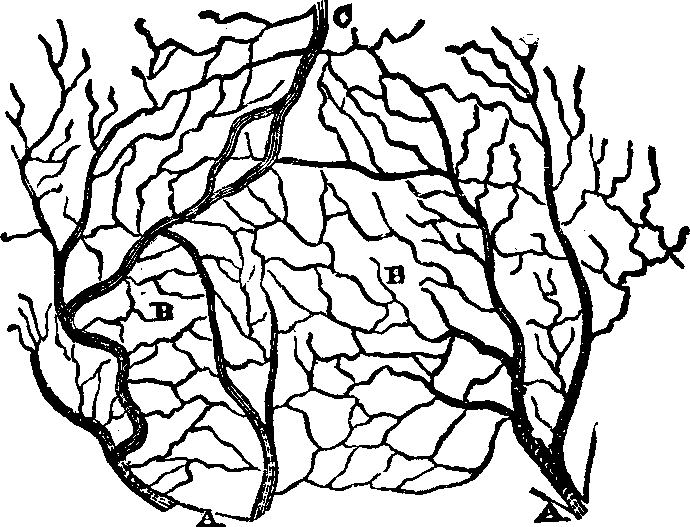

The Lymphatics are not less important organs in the process of absorption. Nearly every part of the body is permeated by a second series of capillaries, closely interlaced with the blood-vessels, collectively termed the Lymphatic System. Their origin is not known, but they appear to form a plexus in the tissues, from which their converging trunks arise. They are composed of minute tubes of delicate membrane, and from their net-work arrangement they successively unite and finally terminate in two main trunks, called the great lymphatic veins. The lymphatics, instead of commencing on the intestinal walls, as do the lacteals, are distributed through most of the vascular tissues as well as the skin. The lymphatic circulation is not unlike that of the blood; its circulatory apparatus is, however, more delicate, and its functions are not so well understood.

Fig. 36. A general view of the

[pg 51]The lymph which circulates through the lymphatic vessels is an alkaline fluid composed of a plasma and corpuscles. It may be considered as blood deprived of its red corpuscles and, diluted with water. Nothing very definite is known respecting the functions of this fluid. A large proportion of its constituents is derived from the blood, and the exact connection of these substances to nutrition is not properly understood. Some excrementitious matters are supposed to be taken from the tissues by the lymph and discharged into the blood, to be ultimately removed from the system. The lymph accordingly exerts an important function by removing a portion of the decayed tissues from the body.

In all animals which possess a lacteal system there is also a lymphatic system, the one being the complement of the other. The fact that lymph and chyle are both conveyed into the general current of circulation, leads to the inference that the lymph, as well as the chyle, aids in the process of nutrition. The body is continually undergoing change, and vital action implies waste of tissues, as well as their growth. Those organs which are the instruments of motion, as the muscles, cannot be employed without wear and waste of their component parts. Renovated tissues must replace those which are worn out, and it is a part of the function of the absorbents to convey nutritive material into the general circulation. Researches in microscopical anatomy have shown that the skin contains multitudes of lymphatic vessels and that it is a powerful absorbent.